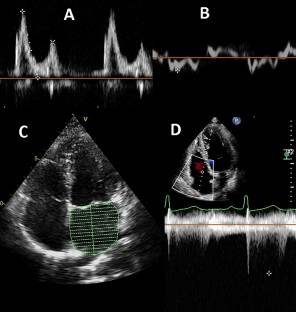

Fig. 1